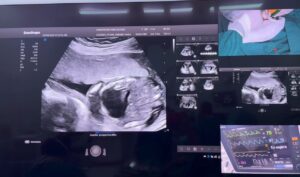

Como parte de la restitución del derecho a la salud y de acercar cada vez más la atención gratuita a

La cirugía fetal intrauterina número 284, se llevó a cabo con éxito en el Hospital Bertha Calderón de Managua, logrando